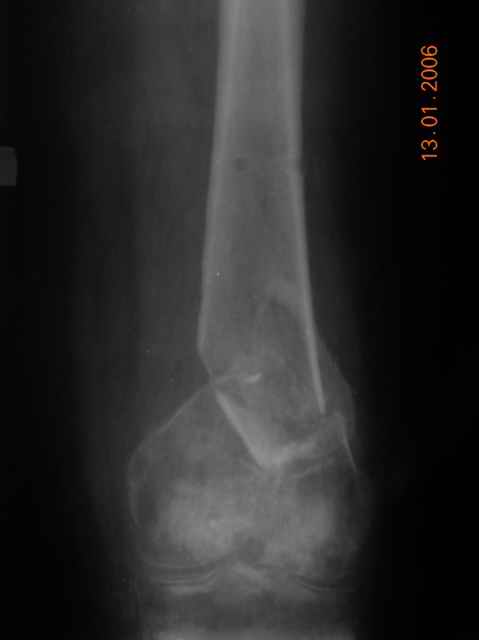

Re: Несросшийся перелом дистального эпиметафиза бедра

Коваленко А.Н. 14 Январь 2006, 18:05

Как раз при ЗИО костная пластика не планируется. ЭОПа у нас нет, поэтому на точку вкола выходим открыто, паралельно хотим удлинить сухожилие. Точно оценить обьем мешает патологичесая подвижность в области несрашения, ~15 гр.Вторая проекция перилагается.